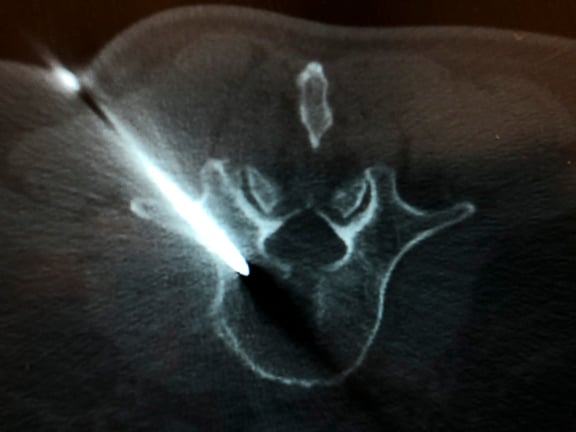

Dr. Massari, a member of the UMass Neurointerventional Radiology Group performed a transpedicular lumbar vertebra biopsy on a patient referred by a local practitioner. Pictured is the radiology team from left to right: Lisa Laprade, procedural technician, Jayne Roose, RN, Kalyn Dhroso, PA, Francesco Massari MD, Amin Chaoui, MD, Danielle McHugh RT CT.